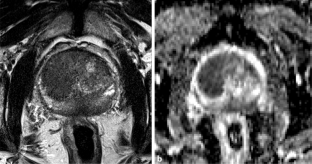

Abb. 1

Abb. 2

Abb. 3

Abb. 4

Abb. 5

Abb. 6